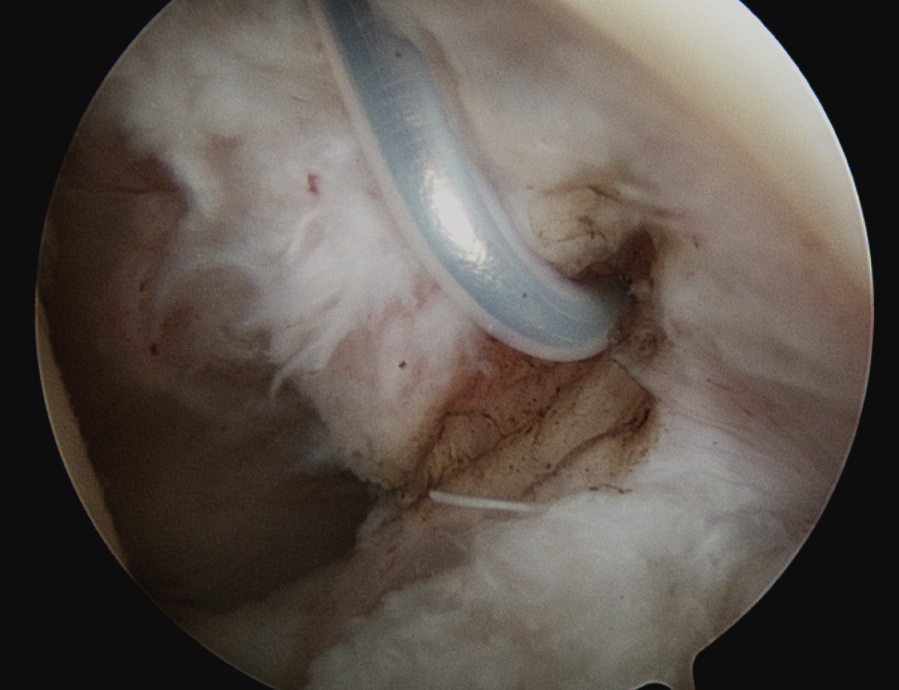

Arthroscopic capsular release

Technique

Release rotator interval - remove all tissue in between biceps and SSC

Mobilze subscapularis front and back from scar tissue

Release anterior IGHL from 3 to 5 o'clock, leaving labrum intact

Release posterior IGHL from 9 to 11 o'clock, leaving labrum intact

+/- release inferior capsule, beware injury to axillary nerve

Rotator interval release

Release anterior IGHL

Release posterior IGHL